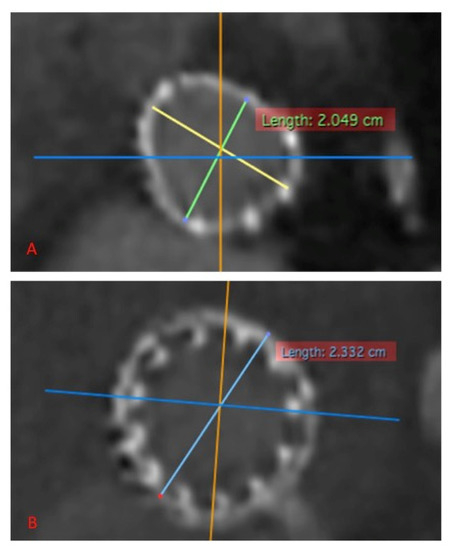

2.2. Technology

2.3. VIV-TAVR Planning and Technical Procedures